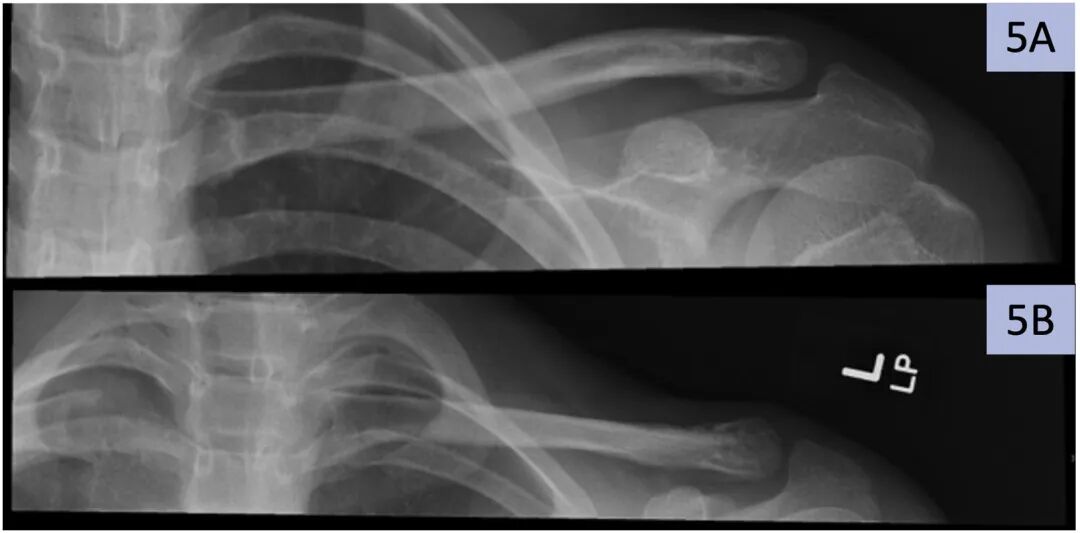

我们描述了一种用于15岁男孩远端锁骨远端骨折的重型、不可吸收缝合修复技术。他在打长曲棍球时摔倒在左肩上后受伤。内侧节段向后和向下移位大约1轴宽(图1、2和3a )。由于骨折模式类似于RockwoodIV型肩锁关节分离,因此需要手术固定。此外,由于患者接近骨骼成熟,移位程度和较差的重塑潜力也有利于固定。由于锁骨远端骨折的碎片尺寸小且植入物移除率高,我们推荐使用不可吸收缝合线修复。

图1。一名15岁男孩跌倒时左侧锁骨远端骨折(箭头)。A)冠状和B)轴向计算机断层扫描。